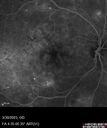

Macular ischemia left eye in type I diabetic (enlarged foveal avascular zone)213 views29 year old female with type I diabetes since age 5. Left eye has enlarged FAZ with vision of 20/20 OD and 20/60 OS. Both eyes have CSME. The left eye did have focal laserApr 12, 2023

Macular ischemia left eye in type I diabetic (enlarged foveal avascular zone)229 views29 year old female with type I diabetes since age 5. Left eye has enlarged FAZ with vision of 20/20 OD and 20/60 OS. Both eyes have CSME. The left eye did have focal laserApr 12, 2023

Macular ischemia left eye in type I diabetic (enlarged foveal avascular zone)216 views29 year old female with type I diabetes since age 5. Left eye has enlarged FAZ with vision of 20/20 OD and 20/60 OS. Both eyes have CSME. The left eye did have focal laserApr 12, 2023